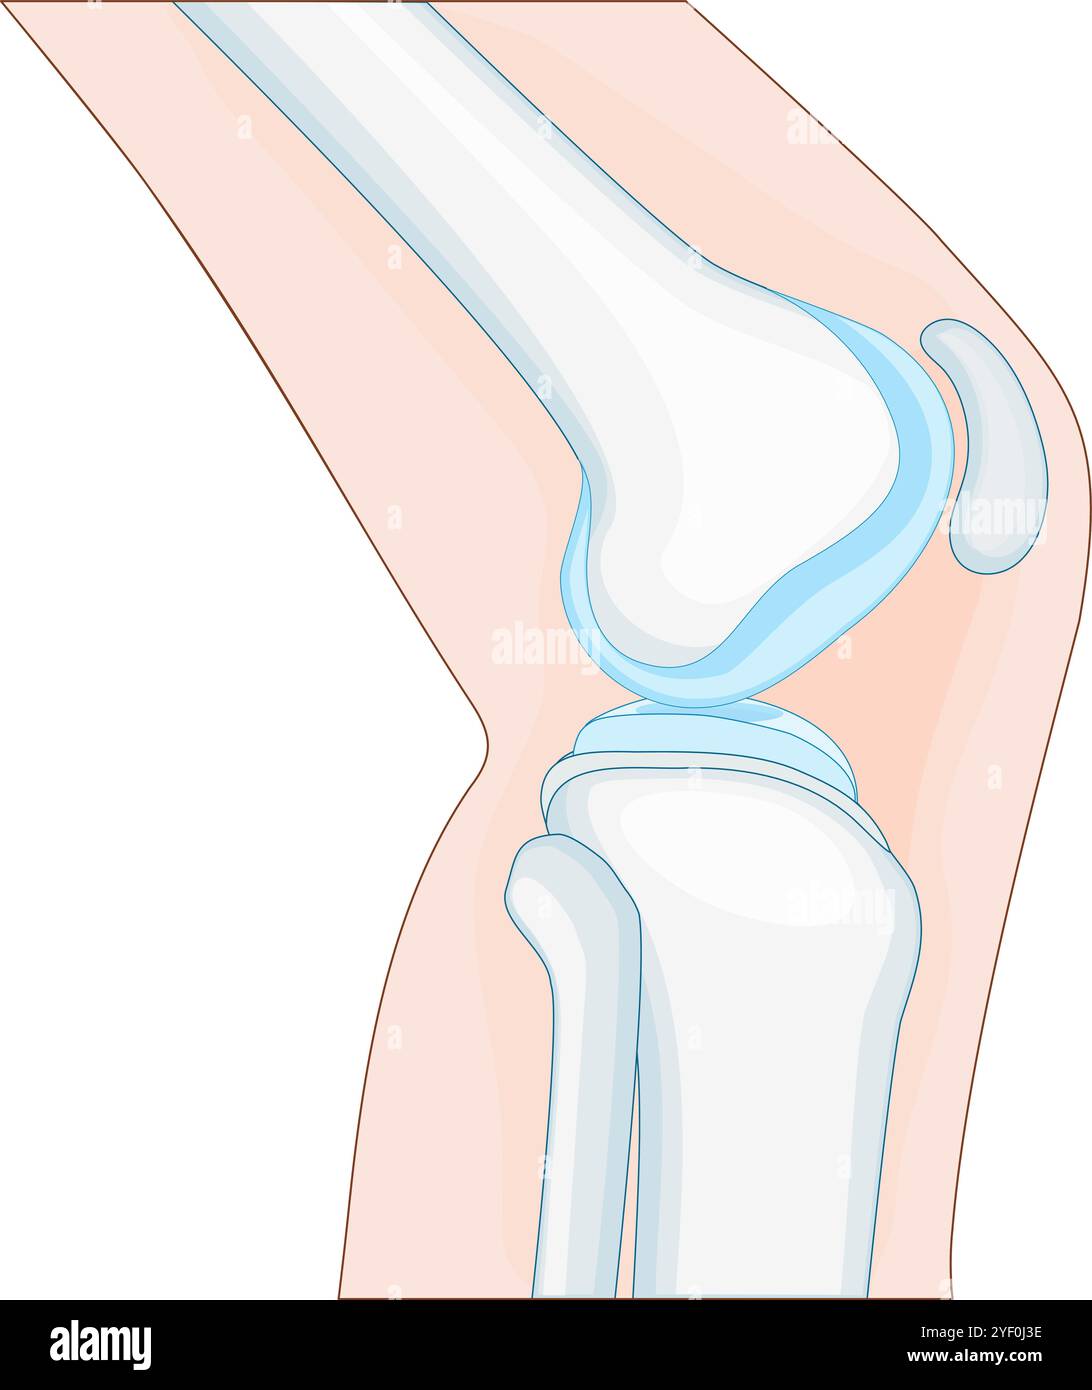

knee anatomy. side view. Cross section of the joint showing the main parts: femur, fibula, articular capsule, menisci, and patella. Vector poster Stock Vectorhttps://www.alamy.com/image-license-details/?v=1https://www.alamy.com/knee-anatomy-side-view-cross-section-of-the-joint-showing-the-main-parts-femur-fibula-articular-capsule-menisci-and-patella-vector-poster-image628807298.html

knee anatomy. side view. Cross section of the joint showing the main parts: femur, fibula, articular capsule, menisci, and patella. Vector poster Stock Vectorhttps://www.alamy.com/image-license-details/?v=1https://www.alamy.com/knee-anatomy-side-view-cross-section-of-the-joint-showing-the-main-parts-femur-fibula-articular-capsule-menisci-and-patella-vector-poster-image628807298.htmlRF2YF0J3E–knee anatomy. side view. Cross section of the joint showing the main parts: femur, fibula, articular capsule, menisci, and patella. Vector poster